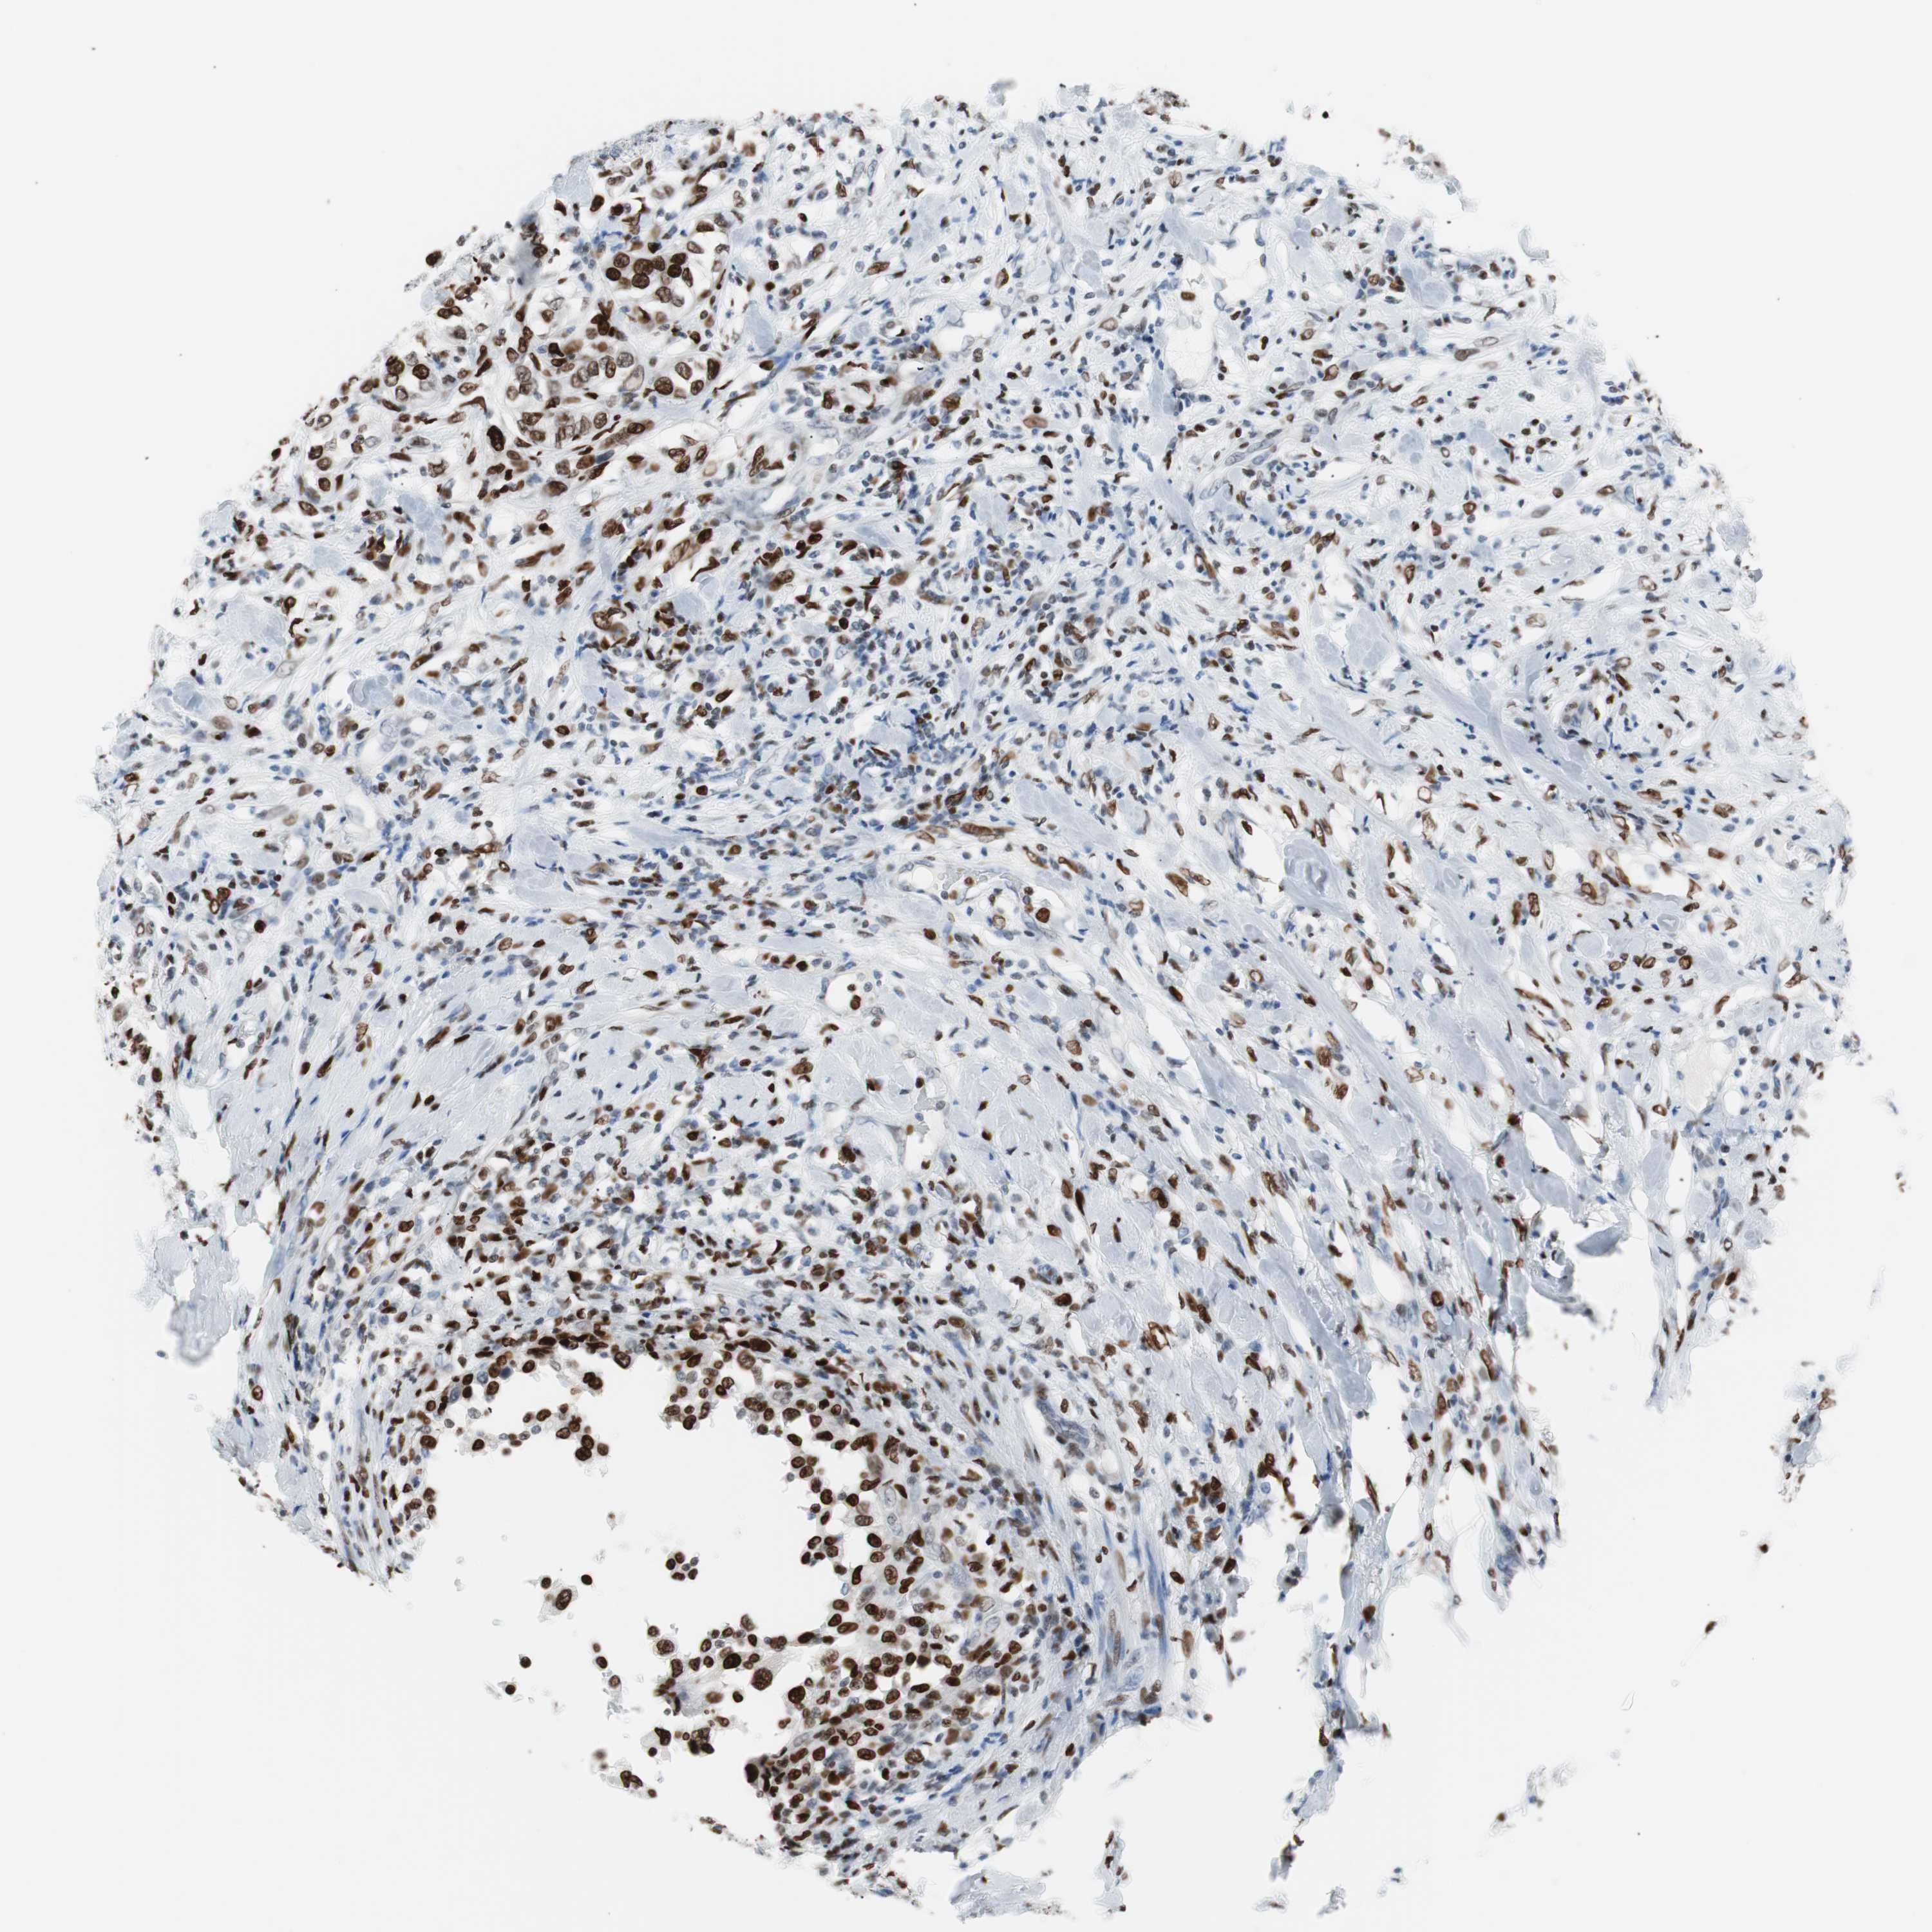

UROTHELIAL CANCER - Protein expressioni

A mouse-over function shows sample information and annotation data. Click on an image to view it in a full screen mode. Samples can be filtered based on level of antibody staining by selecting one or several of the following categories: high, medium, low and not detected. The assay and annotation is described here.

Antibody stainingi

Antibody staining in the annotated cell types in the current human tissue is reported as not detected, low, medium, or high, based on conventional immunohistochemistry profiling in selected tissues. This score is based on the combination of the staining intensity and fraction of stained cells.

Each image is clickable and will lead to virtual microscopy that enables deeper exploration of all samples and also displays staining intensity scores, fraction scores and subcellular localization as well as patient and tissue information for each sample.

Antibody CAB004213

Staining

High

Medium

Low

Not detected

Intensity

Strong

Moderate

Weak

Negative

Quantity

>75%

75%-25%

<25%

None

Location

Nuclear

Cytoplasmic/membranous

Cytoplasmic/membranous,nuclear

Urothelial carcinoma, Low grade

Urothelial carcinoma, High grade